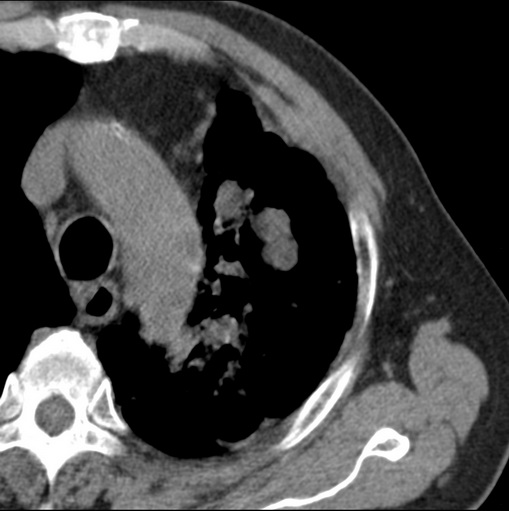

男性患者 81岁 咳嗽 咳痰 咯血

左肺中心型肺癌并:1.左肺阻塞性肺炎;2.纵隔淋巴结肿大;

强化较典型,左上肺癌并纵膈淋巴结转移;左上肺结核并空洞形成;胸膜增厚.

考虑左上肺癌并阻塞性肺炎,左肺转移、左肺门及纵隔淋巴结转移。

标题: 考虑左侧中央型肺癌可能性大

肿块贴近左肺门,包绕左上肺动脉,形态不规则。肿块增强扫描中度强化。纵膈内主动脉弓左旁间隙、气管隆突前、下间隙见多枚淋巴结影。综上考虑左侧中央型肺癌可能性大。图片没有完整上传,尤其是左肺上叶支气管分支层面没有上传,因此不好判断是叶支气管中断还是段支气管中断。另外,下图红色部分所示是“黏液支气管征”吗?